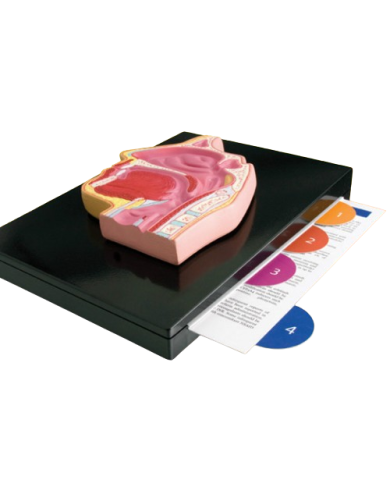

Modello anatomico PER FORNITURE CASE FARMACEUTICHE

Modello anatomico PER FORNITURE CASE FARMACEUTICHE

Modello anatomico PER FORNITURE CASE FARMACEUTICHE

Modello anatomico PER FORNITURE CASE FARMACEUTICHE

Modello anatomico PER FORNITURE CASE FARMACEUTICHE

Modello anatomico PER FORNITURE CASE FARMACEUTICHE

Modello anatomico PER FORNITURE CASE FARMACEUTICHE

Modello anatomico PER FORNITURE CASE FARMACEUTICHE

Modello anatomico PER FORNITURE CASE FARMACEUTICHE

Modello anatomico PER FORNITURE CASE FARMACEUTICHE

Modello anatomico PER FORNITURE CASE FARMACEUTICHE

Modello anatomico PER FORNITURE CASE FARMACEUTICHE

Modello anatomico PER FORNITURE CASE FARMACEUTICHE

Modello anatomico PER FORNITURE CASE FARMACEUTICHE

Modello anatomico PER FORNITURE CASE FARMACEUTICHE

Modello anatomico PER FORNITURE CASE FARMACEUTICHE

Modello anatomico PER FORNITURE CASE FARMACEUTICHE

Modello anatomico PER FORNITURE CASE FARMACEUTICHE

Modello anatomico PER FORNITURE CASE FARMACEUTICHE

Modello anatomico PER FORNITURE CASE FARMACEUTICHE

Modello anatomico PER FORNITURE CASE FARMACEUTICHE

Modello anatomico PER FORNITURE CASE FARMACEUTICHE